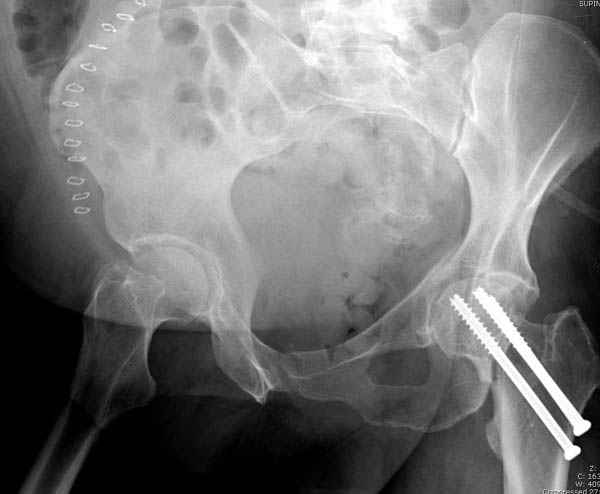

Долгое ожидание повышает риск АВН головки,

рекомендуется ургентная фиксация шейки в первые сутки, а в дальнейшем таз.

В данный момент скелетное вытяжение поучается через перелом шейки, а фиксированный перелом шейки будет участвовать в процессе вытяжения через каннюлированные шурупы.

Перелом шейки смогли зафиксировать через пару дней, ацетабулум до сих пор не оперирован, на вытяжении.

Из-за упущенного времени (три недели с момента

поступления) ацетабулум ведем консервативно.

На снимке ацетабулума редко встречающийся очень низкий перелом, наверное, трудно было репозицию через один доступ? Перелом как бы замкнулся в квадрилатеральной поврехности.